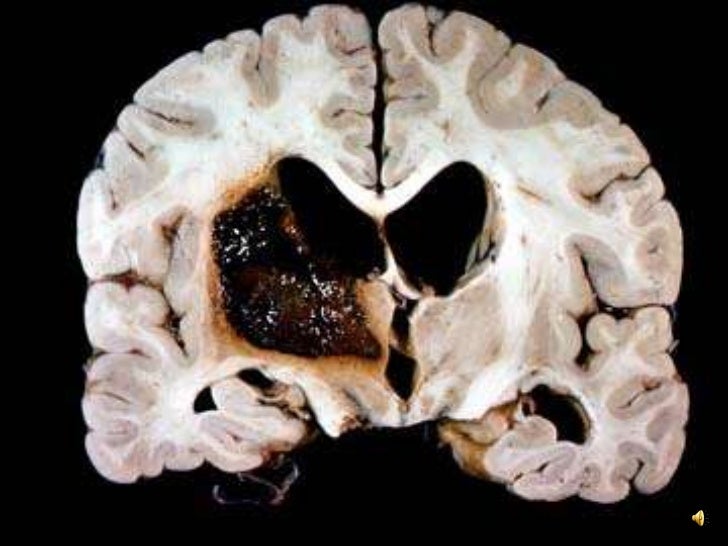

Stroke wikipedia. There are two main types of hemorrhagic stroke cerebral hemorrhage (also known as intracerebral hemorrhage), which is basically bleeding within the brain itself.

Neuroanatomy thesaurus university of massachusetts. Adiadochokinesis. Inability to carry out fast alternating movements which include pronationsupination of the forearm or successive touching of every finger to the thumb. Cerebral infarcts neuropathology. Cerebral infarction is focal mind necrosis due to complete and prolonged ischemia that affects all tissue. Drug abuse and stroke springerlink. Cerebrovascular disorders make a contribution to the morbidity and incapacity related to illicit drug use. Drug abusers have an improved danger of both hemorrhagic and. Stroke wikipedia. There are main kinds of hemorrhagic stroke cerebral hemorrhage (also called intracerebral hemorrhage), which is largely bleeding within the brain itself.